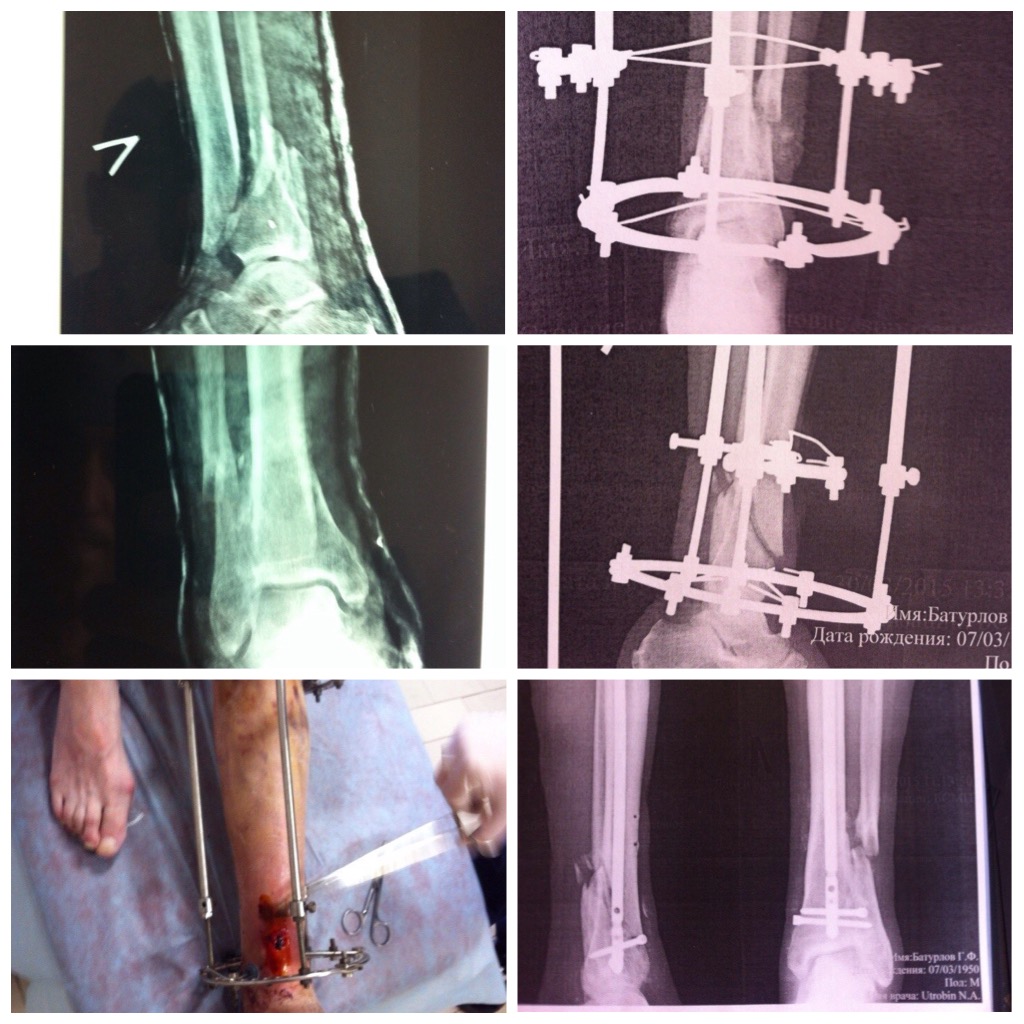

Re: Тугой ложный сустав большеберцовой кости

Пациент, 65 лет, через 2 месяца лечения в ЦРБ(сочетанная травма, лечение в ОРИТ, алкогольный делирий), попал ко мне в палату с переломом 43-А1. Первым этапом, АВФ с остеотомией м/б. Дальше дистракция, репозиция. После восстановления оси, ротации, длинны - БИОС, не снимая аппарат, с рассверливанием и максимально возможным количеством дист. винтов. У Вас можно 3. Не повторяйте моих ошибок - возьмите аппарат с 3мя кольцами, для промежуточных манипуляций (не исключены). И, как видите, у меня сохраняется вальгус. Хотел исправить, но пациент был доволен тем что есть и отказался.